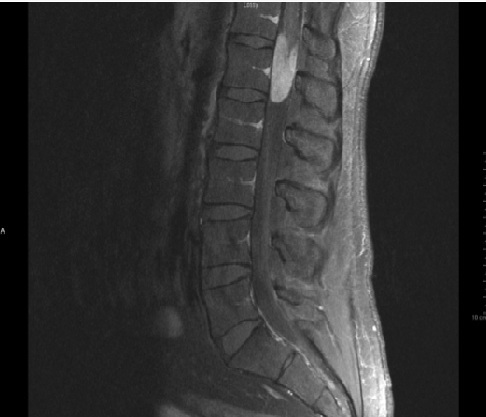

22 tahun menderita cedera tulang belakang setelah jatuh dengan burst fraktur L2 dan canal compromise. Lebih dari setengah dari otot-otot di bawah tingkat cedera memiliki tingkat kekuatan

A. C The correct answer is ASIA C. According to the current (2000/2002 ASIA Standards) the patient meets the criteria for an incomplete spinal cord injury with a “C” classification. As stated, “Motor function is preserved below the neurological level, and more than half of the key muscles below the neurological level have a muscle grade less than 3.” A—Complete injury. No sensory or motor function is preserved in the sacral segments S4-S5. B—Incomplete. Sensory but not motor function is preserved below the neurological level and includes the sacral segments S4-S5. D—Incomplete. Motor function is preserved below the neurological level, and at least half of the key muscles below the neurological level have a muscle grade greater than or equal to 3. E—Normal. Sensory and motor functions are normal.